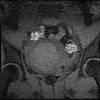

Focused ultrasound surgery (FUS) is a noninvasive image-guided therapy and an alternative to surgical interventions. It presents an opportunity to revolutionize cancer therapy and to affect or change drug delivery of therapeutic agents in new focally targeted ways. In this article the background, principles, technical devices, and clinical cancer applications of image-guided FUS are reviewed.